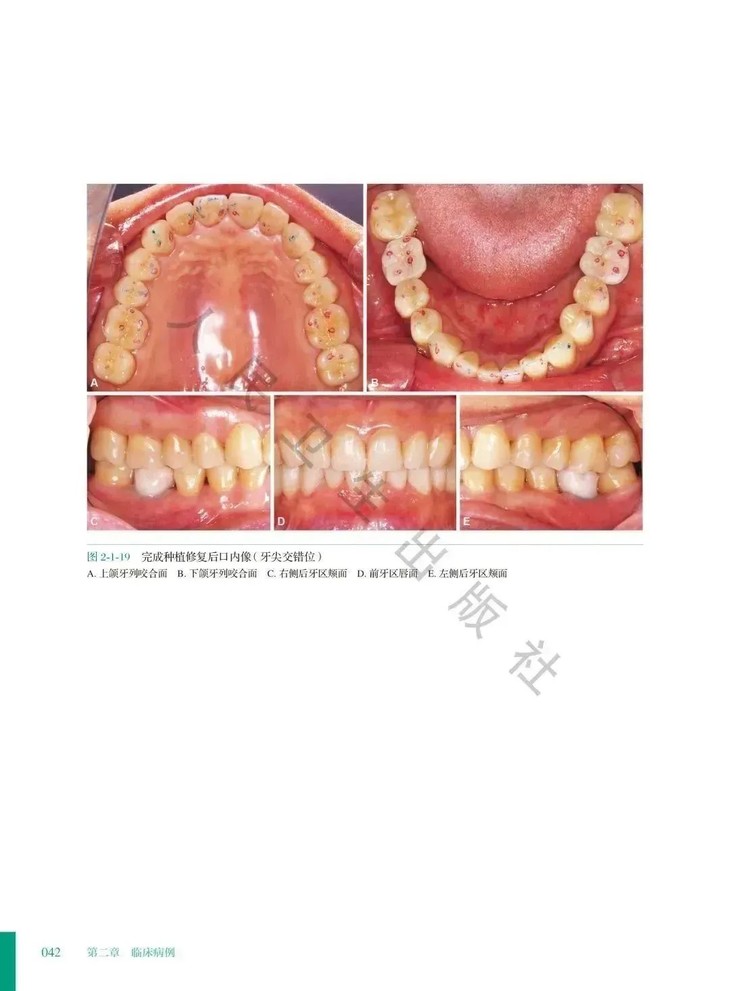

②. 本册收录短面型病例,临床最多见的是前牙磨损。这类病例具有共同的临床特征,可以详细说明治疗方法的共性;每个病例又针对患者各自的特点做了相应的调整,各有侧重。

③.书中以临床病例为载体,重点阐述临床病例的病因与病理生理分析,重点解读临床决策过程,弱化常规的基础临床操作等部分,以求为读者呈现 "从明确病因,到分析病理生理状态,再制订治疗计划,最后长期观察验证治疗计划的正确性"这样一个清晰的临床思维过程,纠正读者对于"咬合重建就是大面积修复"的认识误区,达到正本清源的目的。